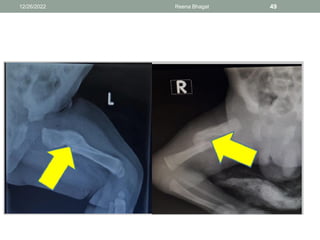

Fracture Bone

• Fractures are rare

• but most commonly affected bones are clavicle, humerus,

femur and those of skull, occasionally spinal fracture may

occur.

Diagnosis

• History: difficult birth

• Physical examination: displacement of bone from its normal

position. Pain(cry) when limb or shoulder is moved. Lack of

movement or asymmetrical movement of limb. Swelling

over bone.

• X-ray

Femur fracture

• Mid shaft fractures can occur if there is shoulder dystocia

or during a birth by the breech when the extended legs are

brought down and born.

• Considerable deformity is evident on examination and the

baby will be reluctant to move the leg lowing to the pain.

Management

• Radiographic studies of the limb confirm the diagnosis

and distinguish this condition from septic arthritis

• Careful handling, cleaning and dressing of te baby to

reduce discomfort.

12/26/2022 Reena Bhagat 48